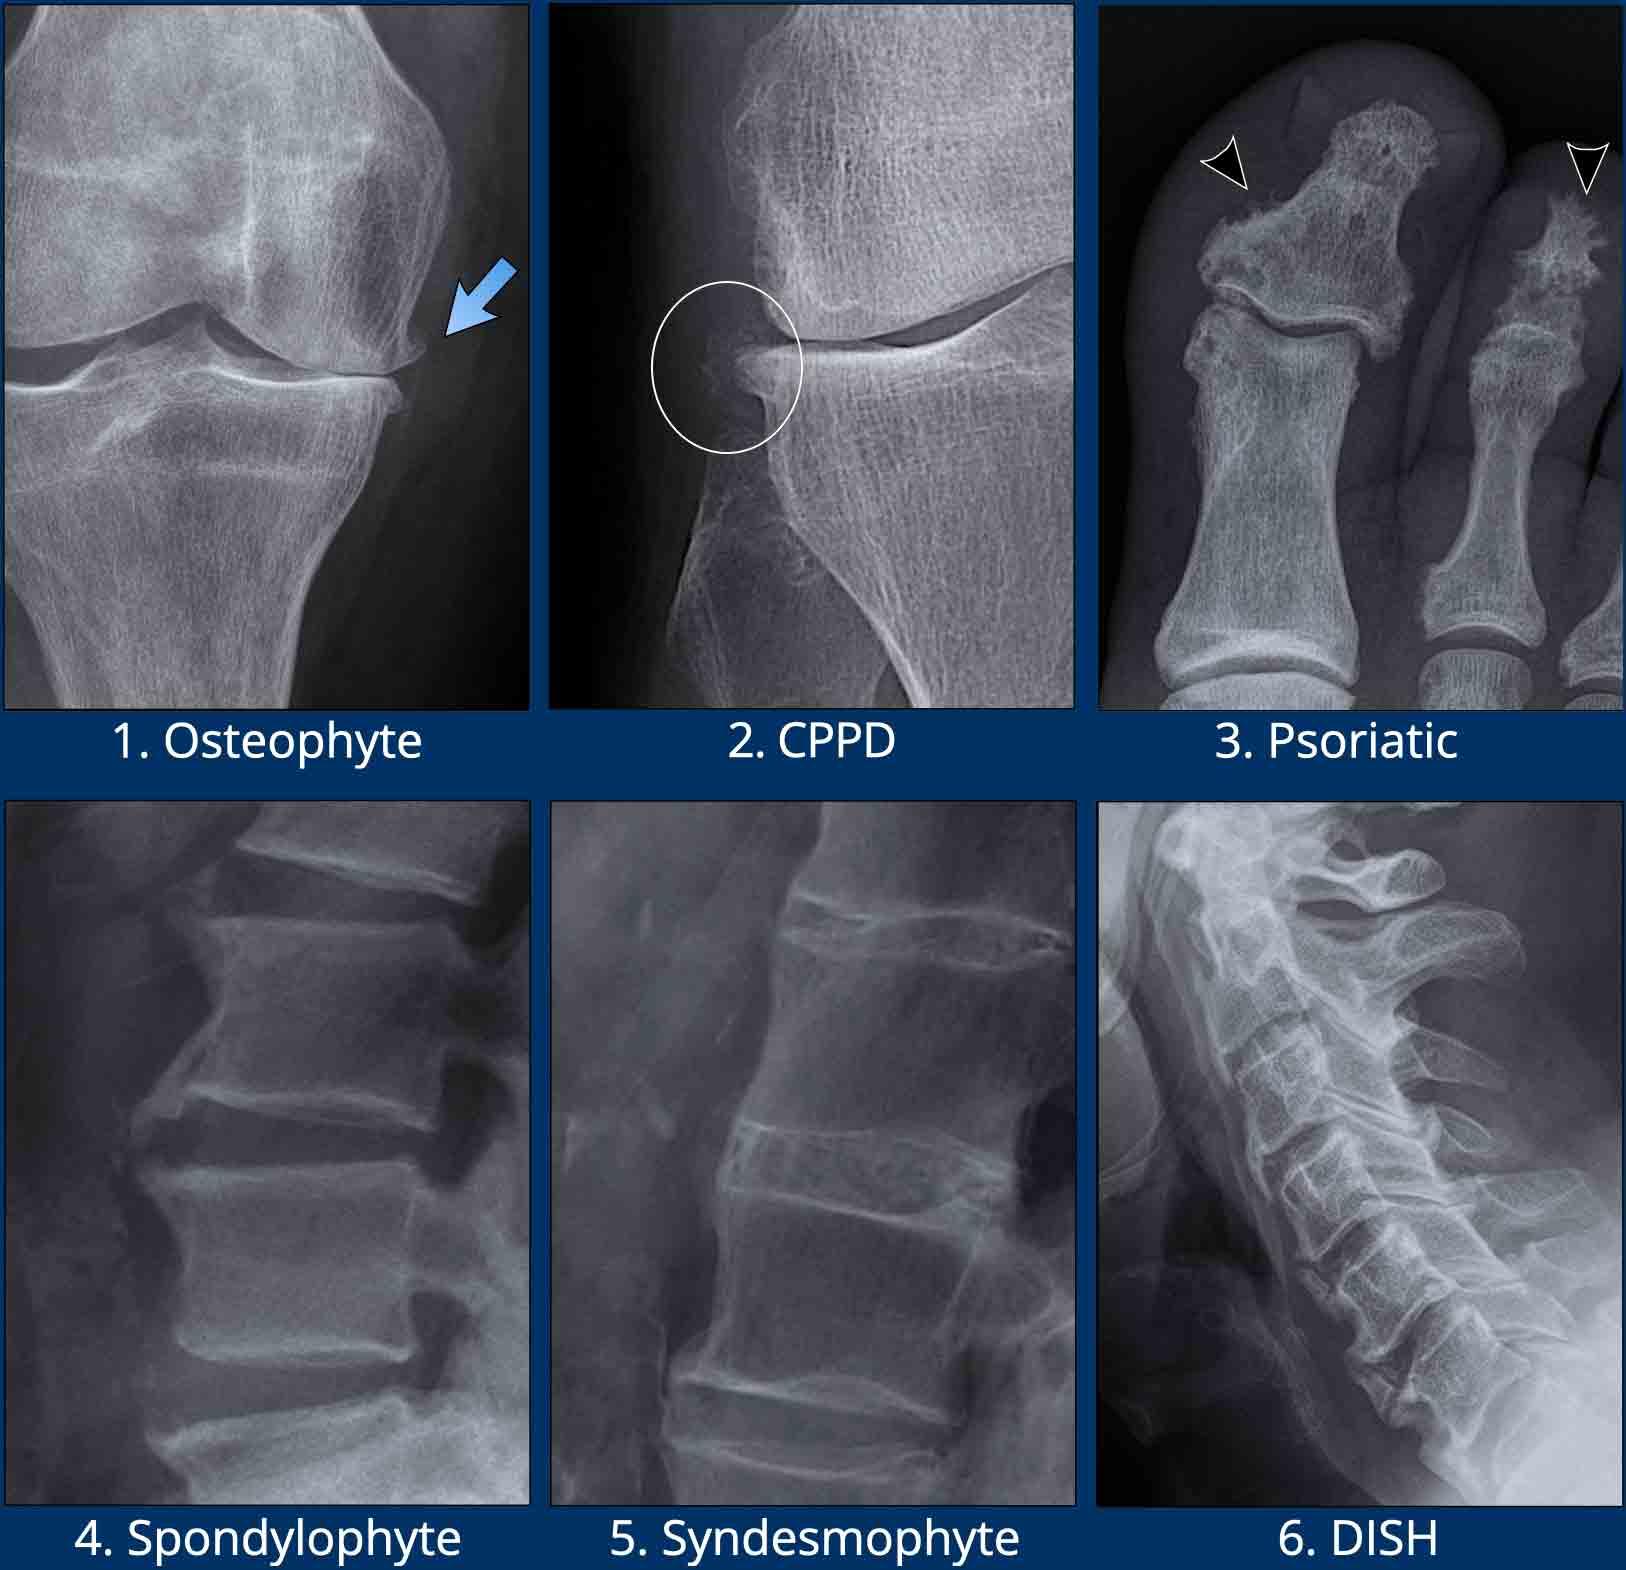

Xương – tăng sinh

Tăng sinh hoặc tạo xương mới gặp trong nhiều bệnh lý khớp, đặc biệt trong viêm xương khớp, DISH và viêm cột sống thể huyết thanh âm tính như viêm cột sống dính khớp và viêm khớp vảy nến.

Tăng sinh xương KHÔNG xuất hiện trong giai đoạn hoạt động của viêm khớp dạng thấp.

Hình ảnh

- Gai xương trong viêm xương khớp.

Tăng sinh xương phát triển tại bờ khớp hoạt dịch, thứ phát sau tổn thương sụn khớp trong viêm xương khớp. - Gai xương ở bệnh nhân CPPD.

Lưu ý các vôi hóa mô mềm (vòng tròn). - Tăng sinh xương trong viêm khớp vảy nến.

Đôi khi được mô tả là viêm màng xương dạng bông tuyết (đầu mũi tên). - Gai xương cột sống (Spondylophytes)

Gai xương tại cột sống trong thoái hóa cột sống. Hướng điển hình là nằm ngang / vuông góc với cột sống. - Cầu xương cạnh đốt sống (Syndesmophytes)

Cốt hóa cạnh đốt sống trong các dây chằng cột sống. Hướng điển hình là thẳng đứng / song song với cột sống. Đây là dấu hiệu đặc trưng của viêm cột sống dính khớp. - DISH

Cốt hóa dây chằng dọc trước. Các cốt hóa này có hình thể to hơn so với cốt hóa trong viêm cột sống dính khớp.